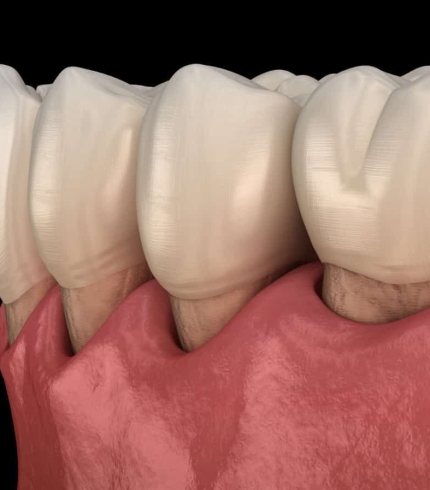

Çene kistleri büyürken herhangi bir klinik bulgu göstermezler ve ağrı yapmazlar. Kist büyüme sonrasında şişlik olarak kendini göstermektedir. Ağrı yapan kistler enfeksiyon belirtisi göstermektedir. Kist büyüdükçe daha büyük sorunların oluşmasına yol açmaktadır. Sinir üzerine baskı yapan kistler alt dudağın uyuşmasına sebep olurken daha da büyüyen kistler dişlerin sallanmasına ya da kendi kendine oluşan çene kırıklarına sebep olabilmektedir. Uzman cerrahi müdahalelerle Çene Kisti Operasyonları başarılı bir şekilde yapılmaktadır. Bu alanda en iyi hizmet veren hekimler arasından bir doktor ekibine sahip İlkdent Diş Kliniğimiz son derece profesyonel ve özenli bir hizmet sunmaktadır.